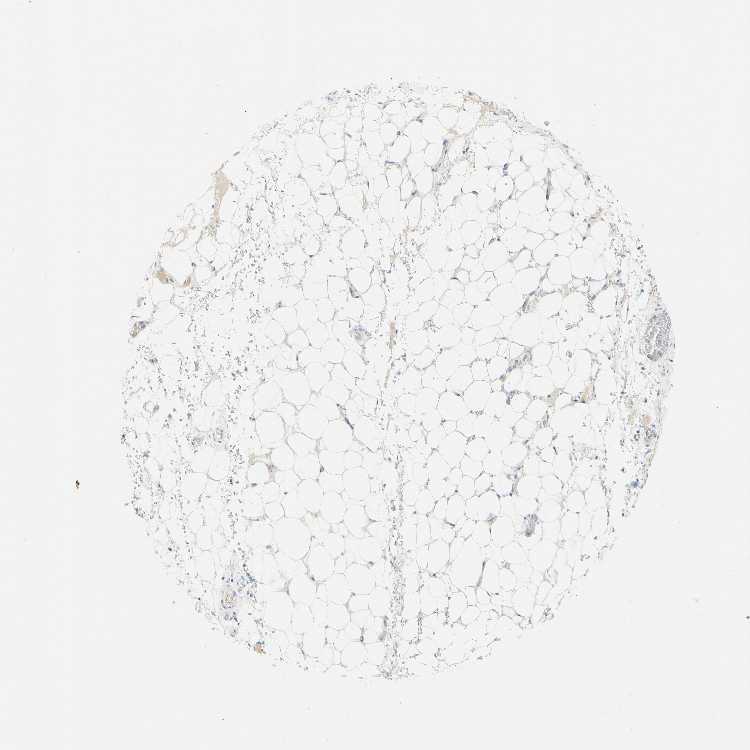

SOFT TISSUE 2 - Antibody stainingi

Antibody staining in the annotated cell types in the current human tissue is reported as not detected, low, medium, or high, based on conventional immunohistochemistry profiling in selected tissues. This score is based on the combination of the staining intensity and fraction of stained cells.

Each image is clickable and will lead to virtual microscopy that enables deeper exploration of all samples and also displays staining intensity scores, fraction scores and subcellular localization as well as patient and tissue information for each sample.

Antibody HPA006154Antibody HPA012012Antibody CAB009454

Fibroblasts Not detectedNot detectedNot detected

Peripheral nerve -Not detected-